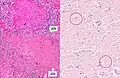

Histopathology, showing epithelioid granulomas with multinucleated giant cells and acid-fast bacilli

Histopathology, showing epithelioid granulomas with multinucleated giant cells and acid-fast bacilli